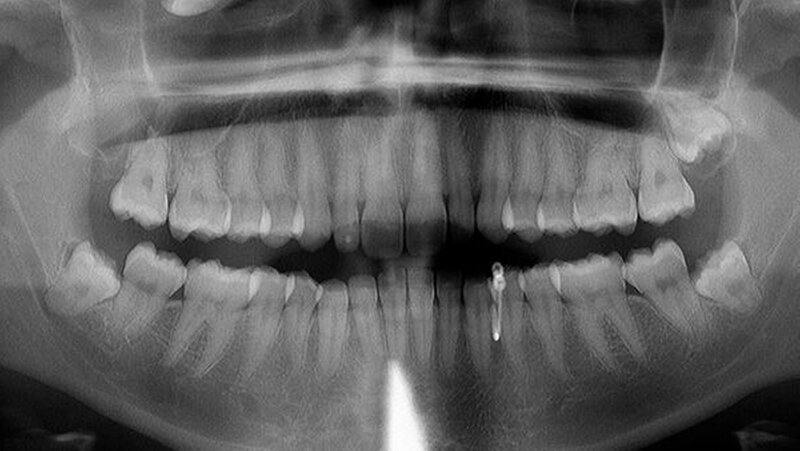

Röntgen (OPG Abb.1): verschattete Kieferhöhle rechts mit extrem verlagertem Zahn 18 direkt infraorbital

Nach erfolgtem Eingriff unter stationären Bedingungen konnte die Nachbehandlung ambulant in unserer Praxis erfolgen und gestaltete sich im wesentlichen störungfrei. Die Röntgenkontrolle nach vier Jahren zeigte operationsbezogen einen Normalbefund (Abbildung 4): Kieferhöhlen rechts und links (soweit beurteilbar) lufthell, Zähne 28, 38, 48 in etwa orthograd (also: Verlaufsbeobachtung vertretbar).